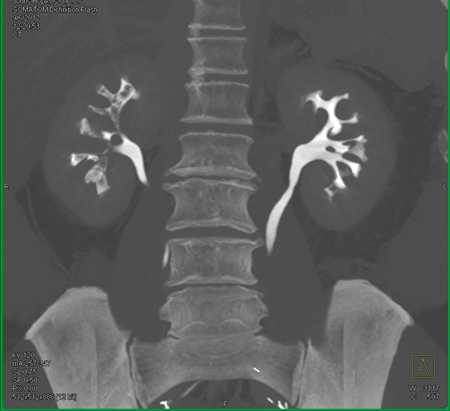

Below is a selection of radiological images of the urinary tract.

Figure 1.

- What do the two clinical images represent in Figure 1?

- What are the possible causes?

-

Papillary necrosis.

POSTCARDS: Pyelonephritis, Obstruction, Sickle cell disease, TB, Cirrhosis, Analgesia abuse, Renal vein thrombosis, Diabetes, Systemic vasculitis.